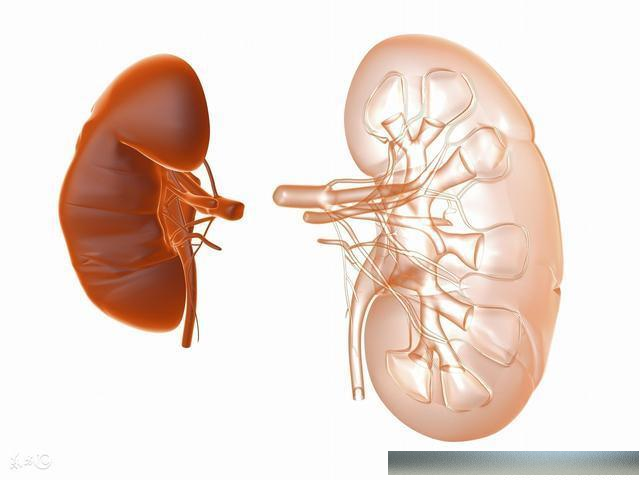

而经常大量饮酒的人,肾脏的负担也会过重,酒精代谢产生的毒素也会损伤肾组织,使得人得肾病的可能性大大提高.

李辉明解释,由于患者本就有多年糖尿病、高血压基础病史,属于高危群体,比起一般人更易发生感染,加上气温升高,老人长期留居在家,运动少,加速了结石的形成、析出,其一旦发病会比其他人更急、更快.